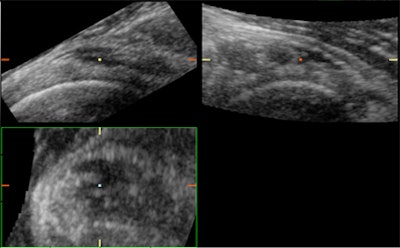

![]() |

| 3D US and multiplanar imaging of the subscapularis tendon of the rotator cuff in a patient suffering from tendinitis. All three planes show signs of tendon irregularity, enlargement, and dishomogeneity. Multiple focal calcifications are seen in all planes throughout the entire tendon fibers. The use of 3D reconstruction of the same subscapularis tendon demonstrates more clearly the full extent of focal calcifications, tendon irregularity and enlargement, and tendon dishomogeneity. All images courtesy of Dearbhla O'Dwyer and Dr. Stefano Ciatti. |